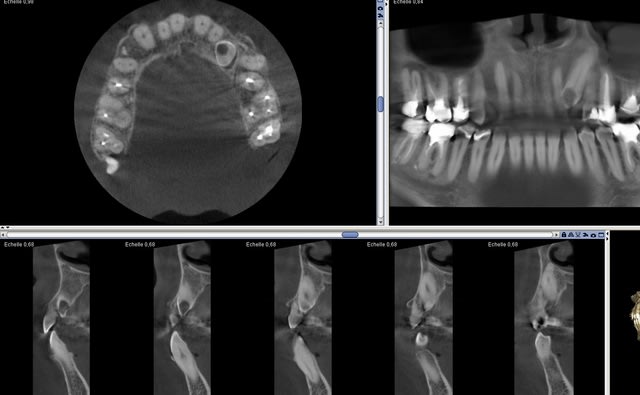

Un cône beam à 5 ça passe quand même mieux que tout seul!!!

> Un cône beam à 5 ça passe quand même mieux que tout seul!!!

Un cone beam ca se paye presque tout seul, tout seul.

Un capteur rvg ca se paie tout seul (minimum 4 radios par patient et maxi 14 en fonction de la situation clinique) et ca paie meme tout un cabinet en plus. J'ai des doutes quand au cone beam dont les indications HAS sont limitées. . -))))

Pour les deux j'ai coté un cbct tarif sécu.. Je dois en faire 4-5 / mois, plus une vingtaine de panos. Leasing payé.

Pas si limitées que ça quand tu les connais

Pardon , Illimitées en NPC. -))))